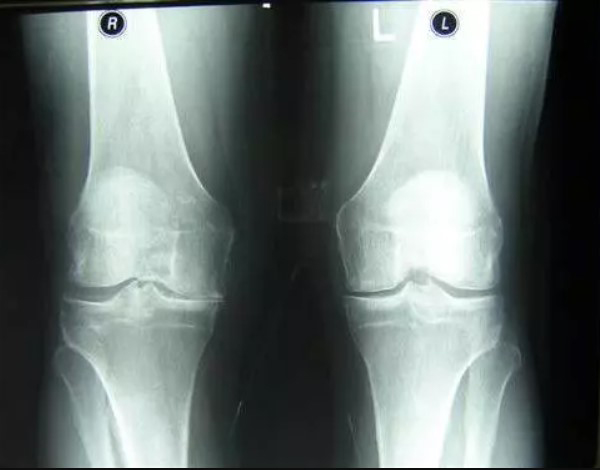

Femme de 54 ans. Son articulation est entièrement restaurée. La durée du traitement : 14 jours :

Traitement de l'articulation de la hanche d'un patient âgé de 44 ans. La douleur atroce qui a torturé le patient pendant 2 ans, a été complètement guérie :

Restauration de l'articulation du coude. Patiente, 31 ans. Durée du traitement par la Voralis Сonfort : 12 jours. Son articulation est entièrement restaurée :